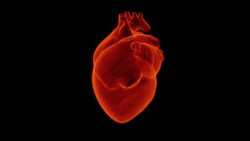

El CNIC coordina `Resilience`, un proyecto diseñado para reducir la insuficiencia cardiaca en pacientes con cáncer

La Comisión Europea, a través del programa H2020 `Salud, Cambio Demográfico y Bienestar`, ha designado al Centro Nacional de Investigaciones Cardiovasculares (CNIC) como coordinador del proyecto `Resilience`, diseñado para desarrollar una nueva intervención médica destinada a reducir la prevalencia de la insuficiencia cardiaca crónica en los pacientes supervivientes de cáncer.

La insuficiencia cardíaca se asocia a un mayor riesgo de cáncer

Un estudio realizado en más de 200.000 individuos ha descubierto que los pacientes con insuficiencia cardíaca tienen más probabilidades de desarrollar cáncer en comparación con otras personas sin insuficiencia cardíaca. La investigación se ha presentado este viernes en el Heart Failure 2021, un congreso científico en línea de la Sociedad Europea de Cardiología (ESC, por sus siglas en inglés),1 y se publica en `ESC Heart Failure`, una revista de la ESC.